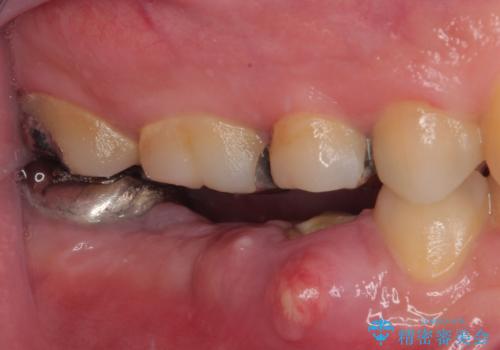

目立つ銀歯と露出した歯根 セラミックでの審美歯科治療

- 奥歯の銀歯とクラウンの縁から見えている歯根を気にして来院された患者様です。

歯根の見えている歯はセラミッククラウンに、詰め物の銀歯が入っている歯はセラミックインレーにて治療を行うこととしました。

笑ったときなど、口を開いたときに目立っていた銀歯や茶色い歯根が気にならなくなり、患者様には大変満足していただけました。